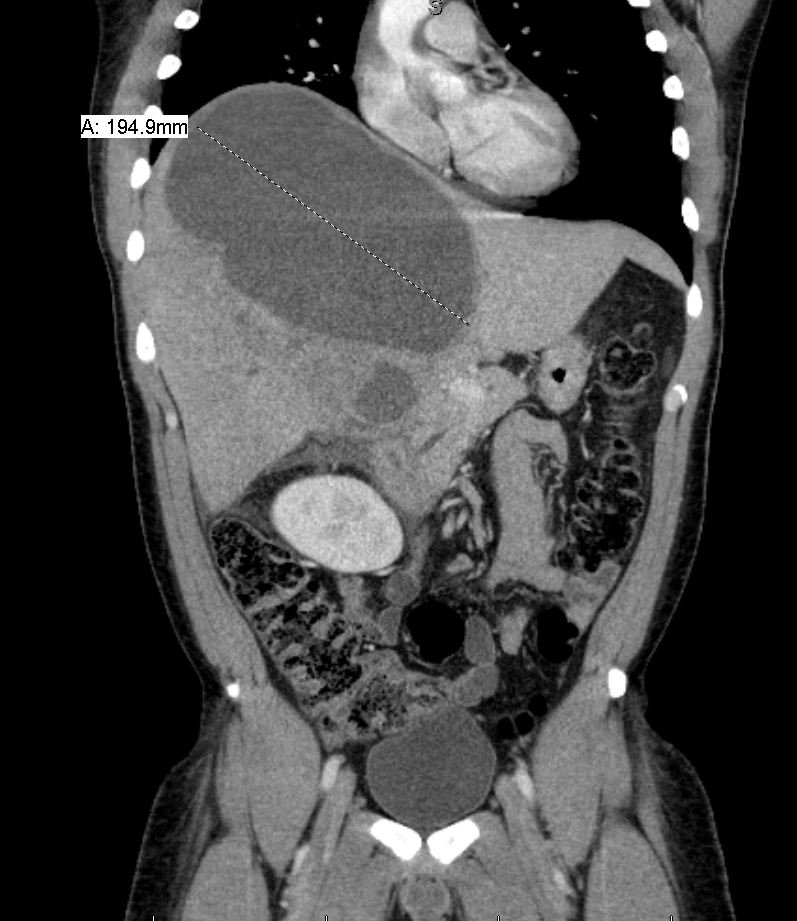

Although rare in the developed world, amebic infections are common worldwide and represent a challenging and often overlooked diagnosis. In this case, an amebic liver abscess was discovered in a 29-year-old male who presented to the emergency department (ED) complaining of right upper quadrant abdominal pain, weight loss, non-bilious/non-bloody vomiting, and diarrhea for three months. He recently traveled to India and Mexico. Point-of-care ultrasound discovered a liver mass and computed tomography (CT) confirmed the presence of a liver abscess. The case highlights the usefulness of ultrasound as an initial diagnostic tool, the importance of careful travel history in patients with suspected infectious diseases, and the initial provision of broad-spectrum coverage for bacterial and amebic pathogens for liver abscesses until the pathogen has been identified.